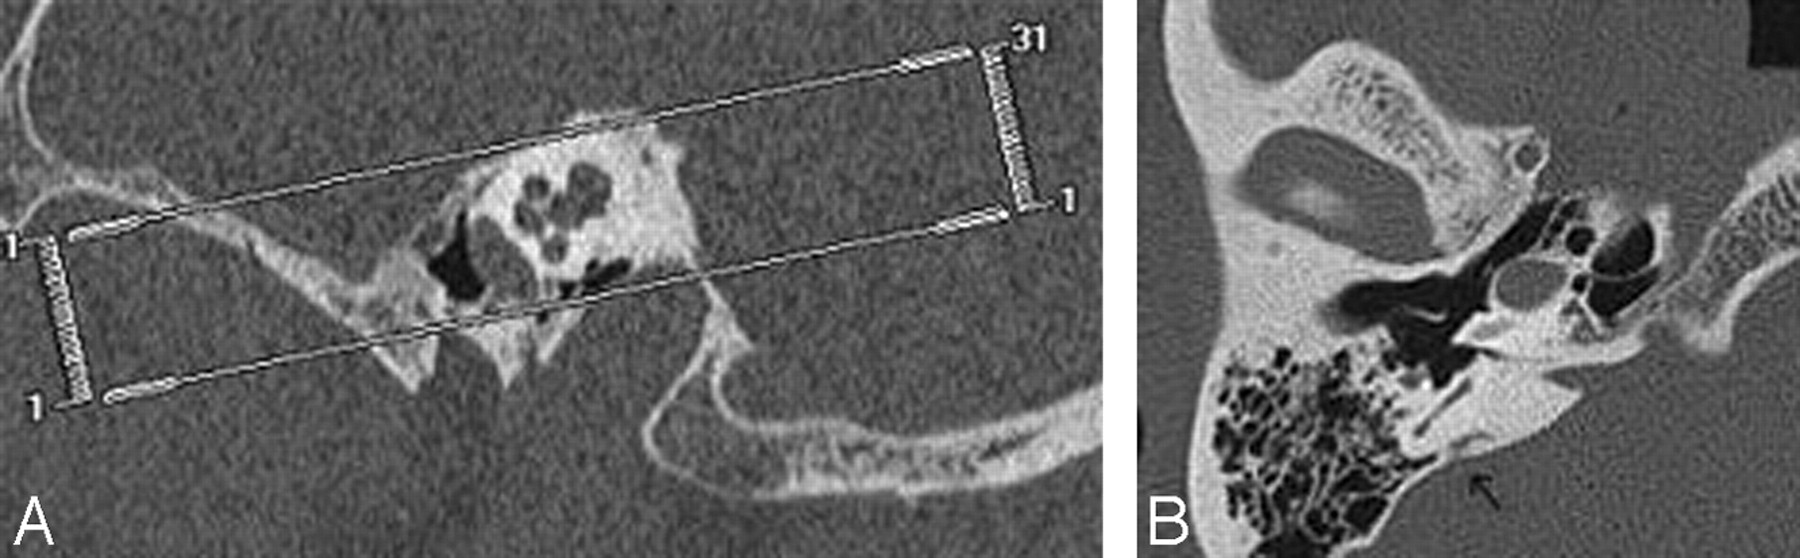

Measurement of the aqueducts: positioning of the measurement bars at the 2 described levels (midportion of the postisthmic segment and external aperture) in (A) and in axial (B, C) reformats.

The method of obtaining measurement at the midpoint varied between the axial and 45° oblique projections. Valvassori et al.12 measured the vestibular aqueduct at the midpoint of the postisthmic segment, which they defined as “halfway between the external aperture and the common crus.” Further reading of their paper shows that these measurements were performed on tomograms, which had been tailored to demonstrate the common crus and the external aperture in the same plane. It is not always possible to visualize both the external aperture and the common crus simultaneously in the axial plane with thin-section imaging. Therefore, for purposes of this study, we estimated the midpoint by scrolling between the common crus and the external aperture and approximating the midpoint visually (Fig 5).

In the 45° oblique plane, the postisthmic aqueduct can be visualized in 1 section, and we determined the midpoint by visually estimating the halfway point between the external aperture and the common crus (Fig 5).